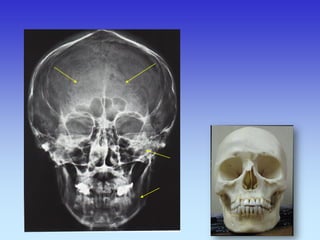

KOSTI GLAVE

Kosti lubanje – rtg.

KOSTI LICA 1. Frontalni sinus 2. Etmoidni sinus 3. Koštani dio nosne pregrade 4. zigomatično-frontalna sutura 5. Maksilarni sinus 6. Zigomatična kost 7. Zigomatični luk 8. Mandibula 9. Donji rub orbite 10. Lijeva orbita

1- Fisura orbitalis superior 2- Foramen orbitalis inferior 3- Foramen mentalis